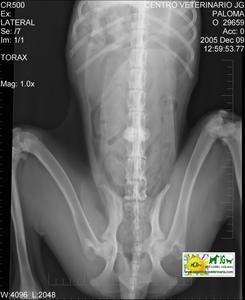

![]() por Juan M. Griñán. Veterinario ![]() comparativa entre una mielografía (mostrando la aguja) y una resonancia magnética, secuencia SE T1w (mostrando donde está el saco dural, sitio para la inyección del contraste). Nótese la extravasación del contraste yodado en la mielografía. | |||||||||